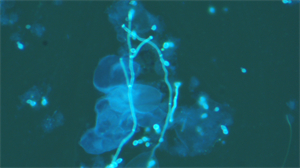

在临床真菌检测领域,精准识别病原体、高效出具报告是诊疗工作的关键。广州明慧公司的正置荧光显微镜UB203i-FL专为真菌检测优化,搭载LED荧光激发模块与高对比度物镜,真菌经荧光染色后,菌丝与孢子可呈现清晰明亮的荧光信号,与背景反差明显,有效减少主观误判。其模块化设计可适配原有显微镜升级,无需整体更换设备,节约投入成本。搭配的图文报告系统,能实时捕获成像、标注关键特征,自动生成标准化报告,大幅缩短报告撰写时间。

成像优化诊断:UB203i-FL专为真菌荧光设计,通过紫外(330-385nm)、蓝色(450-490nm)等多波段激发光系统,分离荧光信号,捕获细胞壁特征,成像效果满足临床微生物荧光检测要求。